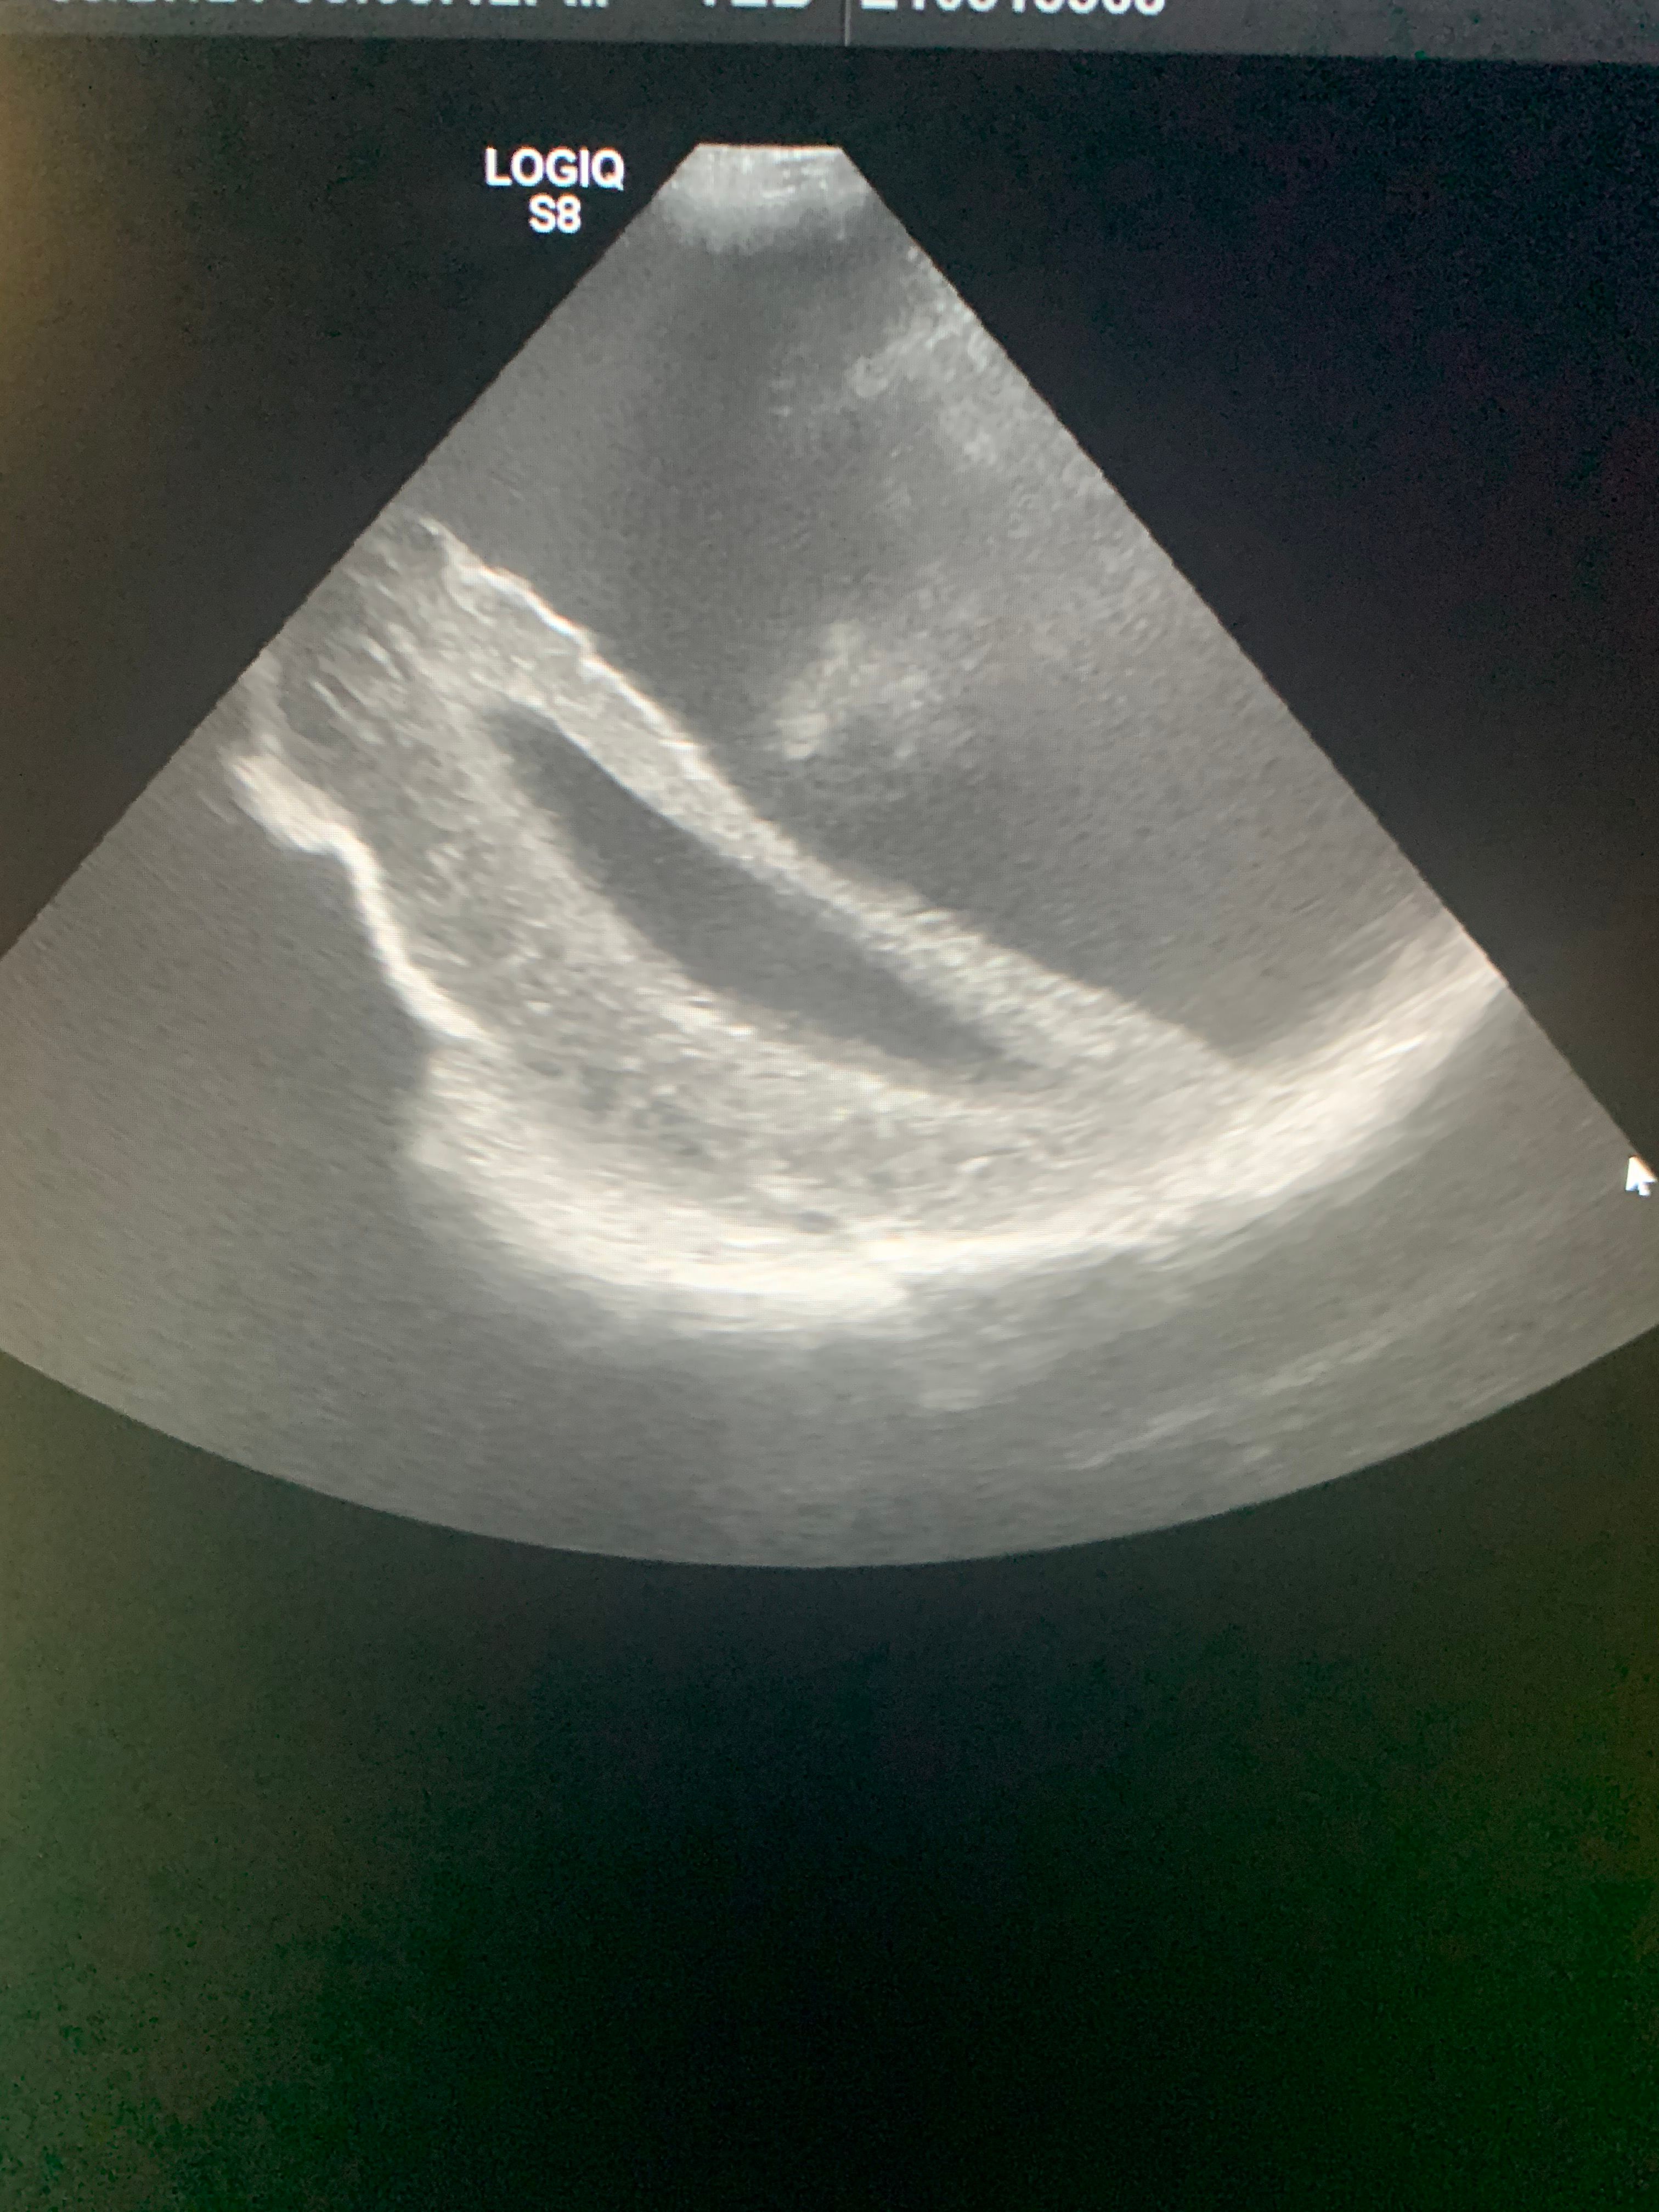

Image IQ Quiz: Infant With Prenatally Diagnosed Abnormality on Ultrasound

40-week-old male with a prenatally diagnosed abnormality on screening ultrasound. What is the diagnosis?

40-week-old male with a prenatally diagnosed abnormality on screening ultrasound. What most likely represents the imaging finding?